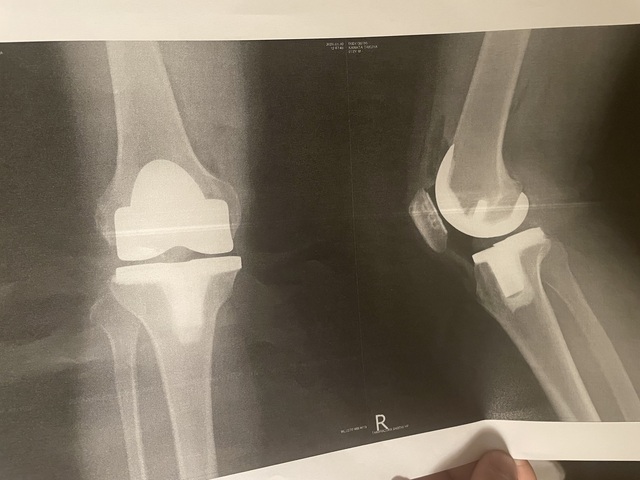

8月にも同様の手術をしたけどそろそろ左脚は不自由のないレベルまで回復したので、こんどは右脚、今日やりました病院も同じで先生も一緒、看護師さんも同じ階だったんて、「覚えてる覚えてる」とかその他オモロい話で昨日はキャッキャ言ってましたほんで今日30日に手術❗️やっぱり術後の数時間は痛くて辛かったな〰︎呼吸器を入れてた喉と脚関節の手術部、痛み止めの効果なのか4時間後位からずいぶん楽に‥‥おかげさんで晩御飯は完食でした‼️昼間ずっと寝てたから晩は寝られへんです😭せやからこんなん書いてます!せやけど正直、もうやりたないわー

関節骨は金属、関節はポリエチレン ですからね!

人工膝関節の耐用年数は25年間位そうです

国民健康保険の高額医療制度、保険会社生命保険を使うと、人にもよるが脚片方で170万円ほど医療費として掛かるところ10万円位ですませることも可能です、私の場合は生命保険の特約が大きくて、給付金で黒字でした。